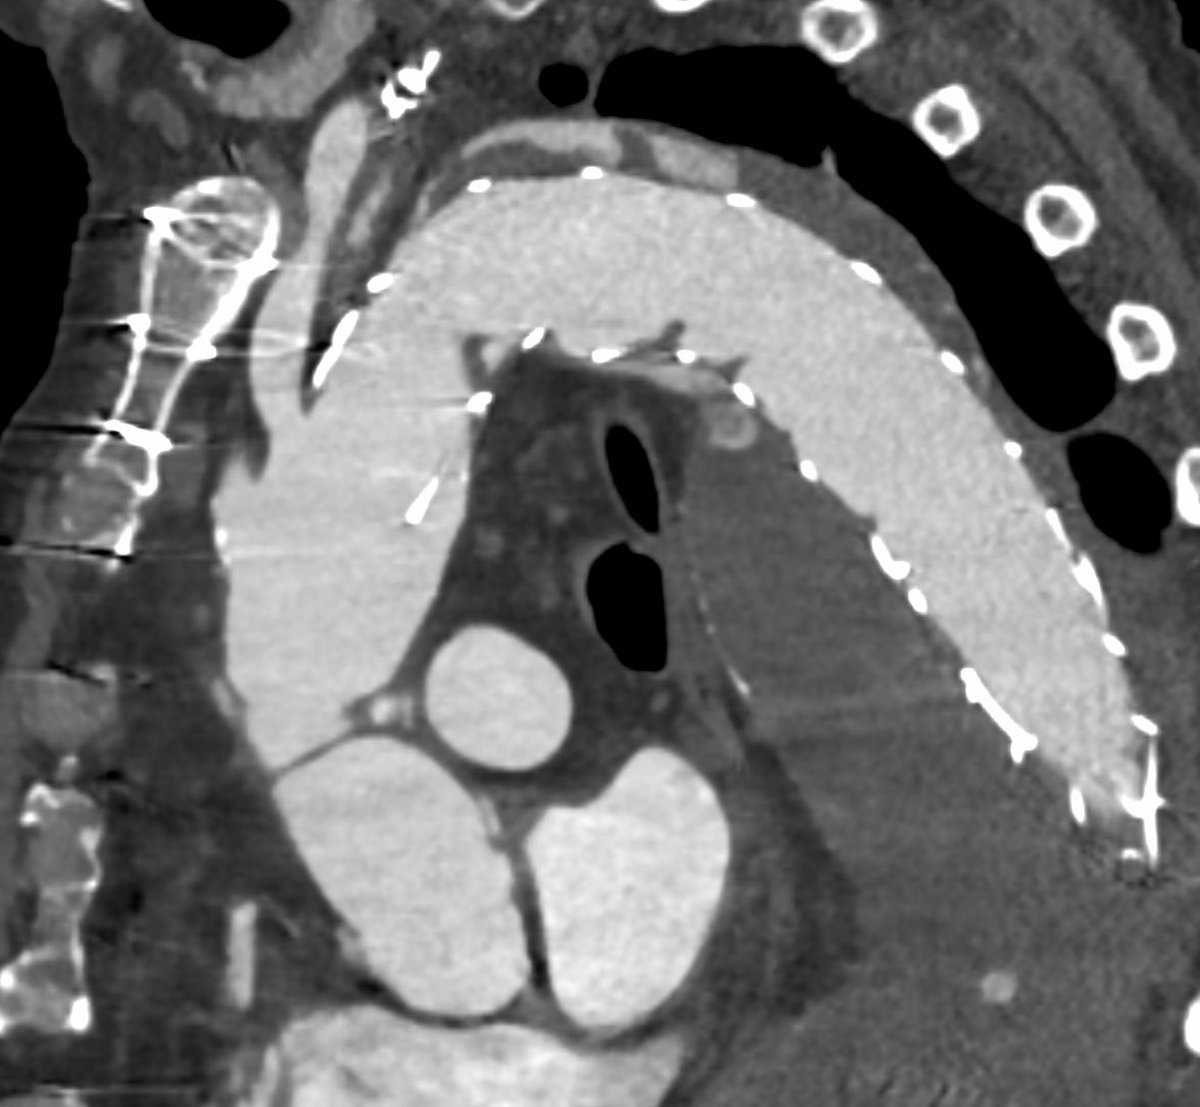

Type 1A endoleak with a short ascending graft and expanding arch. Our team’s first experience using the Bolton Arch graft. Really precise deployment and easy cannulation of the tunnels @TerumoAortic @CAIRweb #aorta